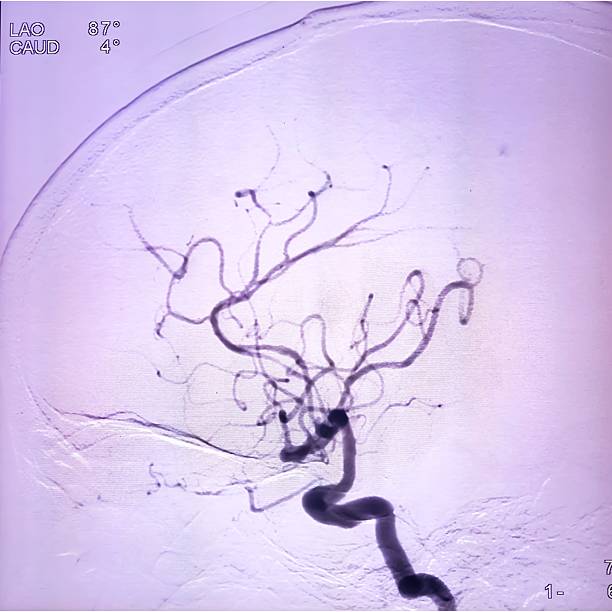

🟢 뇌경색이란 무엇인가요?

뇌경색은 뇌혈관이 막히면서 해당 부위에 혈액이 공급되지 않아 뇌세포가 손상되는 질환이에요.

**‘허혈성 뇌졸중’**이라고도 하며, 전체 뇌졸중의 약 **70~80%**를 차지할 만큼 흔한 형태입니다.

보통은 고혈압, 당뇨, 고지혈증, 흡연, 심장질환 등이 주요 원인으로 작용하죠.